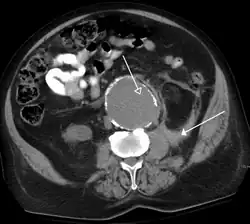

- Tomografia Computadorizada

A Tomografia Computadorizada (TC), também conhecida como uma tomografia computadorizada, é um método de imagem médica que combina várias projeções de raios-X tomadas de ângulos diferentes para produzir imagens detalhadas de áreas transversais de áreas dentro do corpo. As imagens de CT permitem que os médicos obtenham visões tridimensionais muito precisas de certas partes do corpo, como tecidos moles, pelve, vasos sanguíneos, pulmões, cérebro, coração, abdômen e ossos. A TC também é frequentemente o método preferido para diagnosticar muitos cancros, tais como cancro do fígado, do pulmão e do pâncreas.

A TC é frequentemente utilizada para avaliar:

- Presença, tamanho e localização dos tumores

- Órgãos na pelve, tórax e abdômen

- Saúde do cólon (CT colongraphy)

- Estado vascular / fluxo sanguíneo

- Embolia pulmonar (angiografia por TC)

- Aneurisma da aorta abdominal (angiografia por TC)

- Lesões ósseas

- Tecido cardíaco

- Lesões traumáticas

- Doença cardiovascular